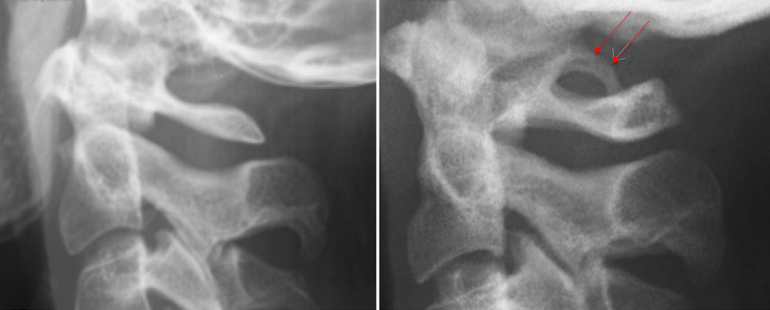

Проведение диагностики

Для установления диагноза назначается рентгенография черепа и шейного отдела позвоночника. Аномалия Киммерли хорошо видна на рентгеновских снимках при исследовании краниовертебрального перехода. Если пациент испытывает шум в ушах, для исключения заболеваний уха, горла и носа необходима консультация отоларинголога. Проводится аудиометрия, а при необходимости могут быть назначены дополнительные методы обследования слуха.

Поскольку данная патология не вызывает синдрома позвоночной артерии, невролог исключает другие возможные причины. Для диагностики тромбоза или аневризмы сосудов головного мозга выполняется ангиография с использованием контрастного вещества. Чтобы оценить влияние синдрома на кровообращение, применяются следующие гемодинамические исследования:

С помощью указанных методов врач может определить область, где происходит сжатие позвоночной артерии, а также её зависимость от различных положений шеи и головы.